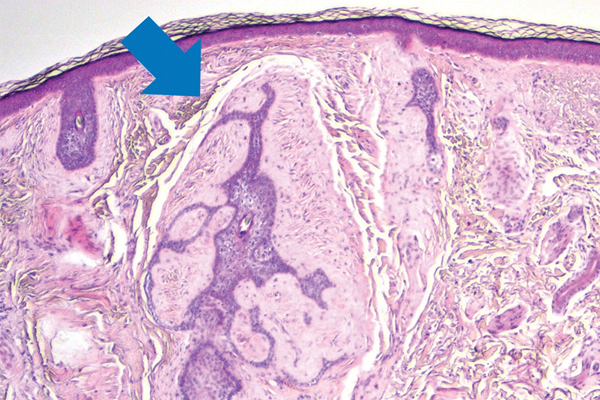

Um homem de 27 anos notou o aparecimento de lesões cutâneas assintomáticas na região perianal precedidas em um dia por cefaleias e febr...